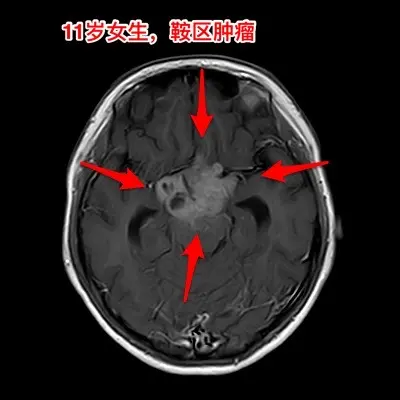

生殖细胞瘤对化疗很敏感,降低颅压才安全。之前我发的11岁四川女孩子,因多饮多尿、视力下降、多睡等症状在我科住院。住院后经用药物治疗,精神状态明显好转。 我们怀疑肿瘤为生殖细胞瘤,因肿瘤体积巨大,综合考虑病史、体检、手术风险、对化疗、放疗的敏感性,我们于8月13日给患儿作了肿瘤活检手术。 手术后病理报告为纯生殖细胞瘤,未见其他肿瘤成分(当然活检取得的标本很少,这个结论不是百分百的可靠) 8月20日开始化疗,8月21日患儿出现精神差、多睡症状,和住院前的症状相似。复查CT显示肿瘤在活检手术后继续增大,而且造成了脑积水,颅压高,见图2。此时不得不为患儿作急诊脑室外引流手术,以求降低颅压,为化疗保驾护航。随后继续化疗。 化疗的第三天,CT显示肿瘤体积有所缩小,见图4。 化疗一周后,肿瘤体积显著变小了,脑积水明显减轻了,见图5。病人的精神状态好转。拔除了脑室引流管。 希望化疗能将肿瘤完全杀灭,再结合放疗,将肿瘤完全治愈。